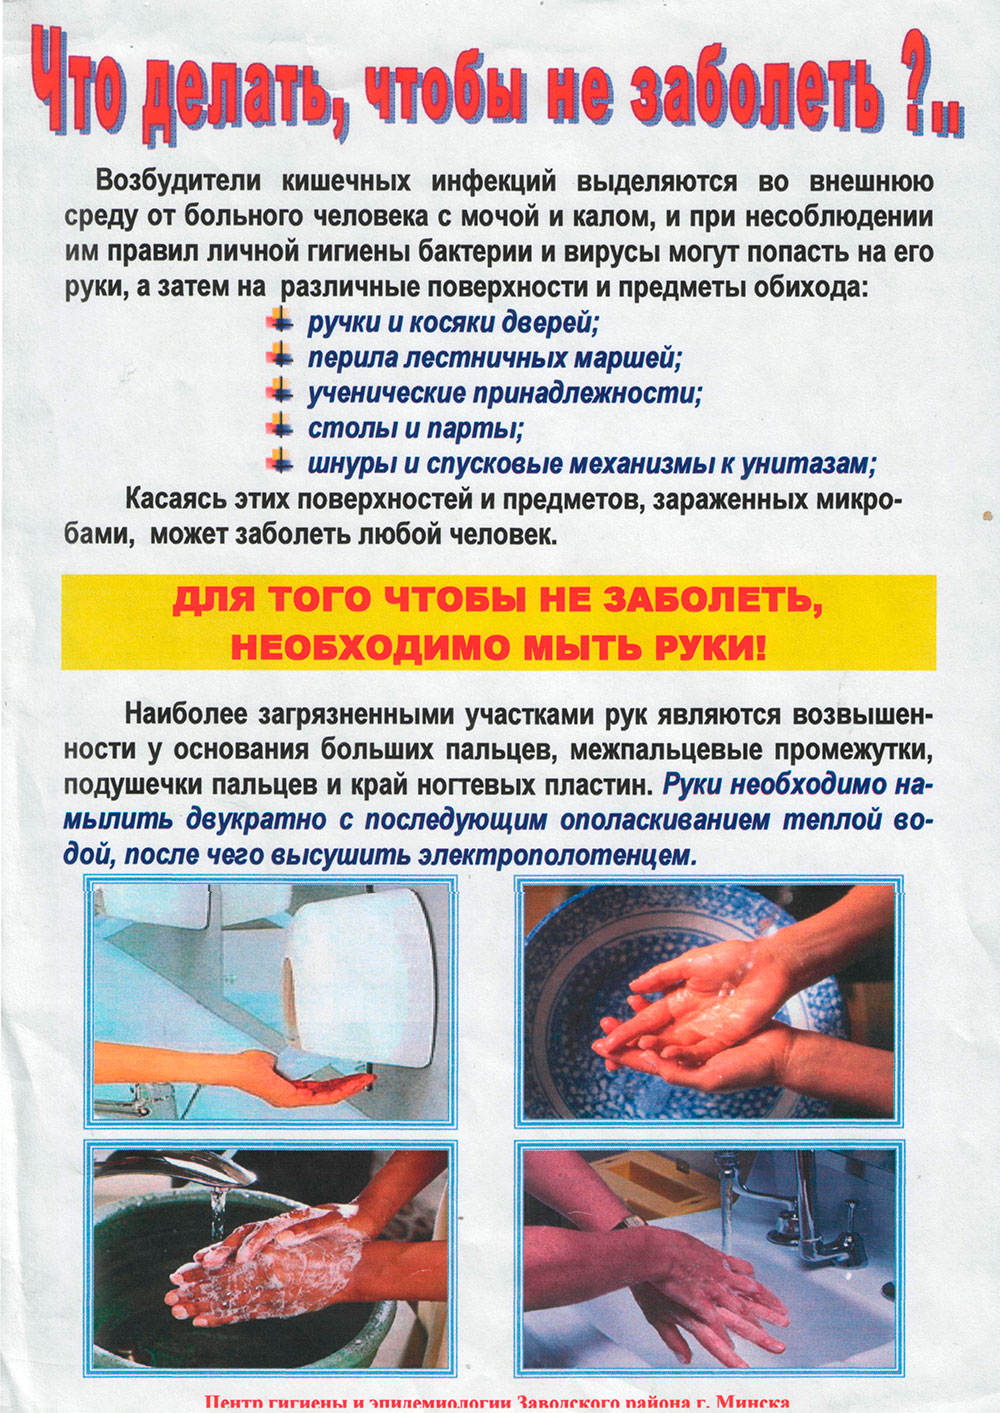

Профилактика кишечных инфекций